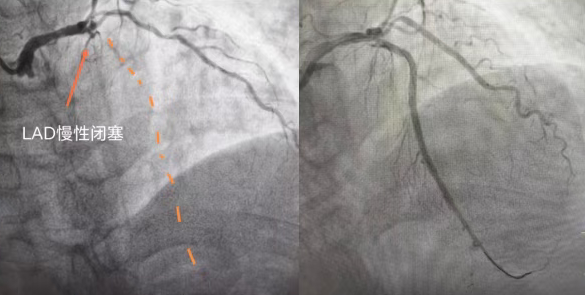

74 岁的陈阿姨(化名),数月来被反复胸痛折磨的寝食难安,稍一活动就胸口憋闷、刺痛难忍,休息后也难彻底缓解。辗转就医后,病情始终未获有效解决,最终在国文医院迎来转机:检查显示其心脏前降支近端钙化并完全闭塞,属于冠心病中难度极高的冠状动脉慢性完全闭塞病变(CTO),堪称冠脉介入治疗的 “最后堡垒”。

心脏正常运转依赖冠状动脉供血,前降支作为冠脉中供血范围最广、最关键的血管,负责心脏前壁、心尖等核心区域供血,一旦堵塞,极易引发大面积心肌缺血、急性心梗甚至猝死。这位老年女性所患的CTO病变,即冠脉完全闭塞超3个月,血管壁伴随大量坚硬钙化斑块,如同心脏“生命干道”被石块堵死,管壁脆硬。

手术由北京专家全程主导,操作精准细致,成功打通闭塞前降支,彻底解决老人心肌缺血问题。术后第二天,老人精神明显好转,可下地活动,家属对专家技术与医院服务充满感激。